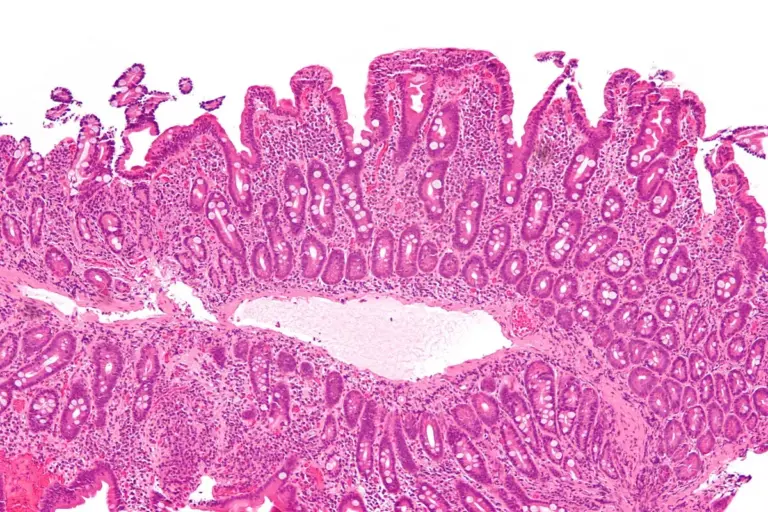

The selection of celiac disease treatments is unique in the medical world because the primary “medicine” is a total and permanent lifestyle change. There are no pills or surgeries that can cure the condition, but strict dietary management is highly effective. The goals of clinical management are to stop the autoimmune attack, allow the intestinal villi to regrow, and correct any nutritional gaps. At Liv Hospital, we provide a multidisciplinary support system to help you navigate this transition, ensuring that your diet is safe, varied, and nutritionally complete.

The cornerstone of recovery is the total elimination of gluten from the environment. This requires a much deeper level of commitment than a standard diet.

In a small percentage of clinical cases, the intestine does not heal despite a strict gluten free diet. This is known as refractory disease.

Restoring the balance of the gut flora is a key therapeutic goal after years of inflammation.